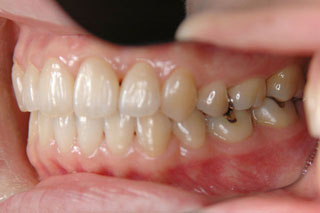

2年半ほどの治療で、装置を撤去し保定治療に移行しています。概ね緊密な臼歯の咬合と前歯の被蓋が確立されました。

保定治療を開始してから2年半が経過していますが、良好な咬合の安定が維持されています。見た目だけではなく、中心位マウントの咬合器にて顎位のズレを計測していますが、計測値は1mm未満の数値である事を確認しています。理想的には中心位=咬合位かも知れませんが、多少の遊びは必ず出てきます。しかしながら最初からルーズなゴールを目指していたら、的を外してしまうでしょう。できれば、ピンポイントで理想を目指したいものです。